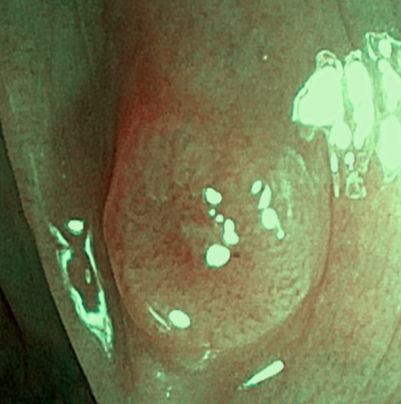

내시경 상 다발성의 대장 용종들이 확인되었으며, 당일 내시경 진행하며 7개 정도의 용종을 절제하였습니다. 환자분 출혈등 합병증 위험 더 커질수 있어 남아있는 대장 용종은 1~2개월뒤 절제 하기로 하였습니다. 대장 용종 조직검사 시행하였으며 7개중 5개가 선종으로 확인되었습니다. 선종은 치료 받지 않으면 추후 대장암으로 진행 가능성 있는 병변으로 주기적 추적관찰이 필요한 병변입니다.

• 대장내시경: 다발성 용종 확인 (NBI 모드) 대장내시경: 다발성 용종 확인 (NBI 모드)